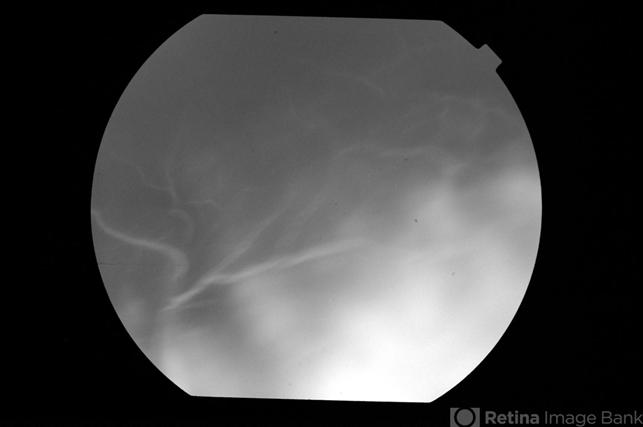

- Uveitis with exudative retinal detachment

- uveitis, exudative retinal detachment

- Fluorescein angiogram of an elderly patient with bilateral posterior uveitis shows massive leak under inferior RD suggestive of severe choroidal inflammation and hyperpermability. He responded well to oral steroids with complete resolution of the uveitis and RD.